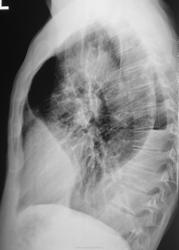

Прошел год, пациент значительно потерял в весе, температура около 38 градусов, кашель с мокротой и был доставлен в рентгеновский кабинет на носилках.

"Ой"! Воскликнули фтизиатры, это наше! На носилках пациент был срочно госпитализирован в областную туб больницу в тяжелом состоянии. Лечение, со слов фтизиатров, было не легким, так сказать - "на грани", пациент был прооперирован.